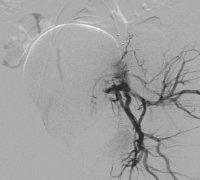

• 女性盆腔血管分布实物图发布日期:2009-06-26 23:29:28

女性盆腔血管分布图 ,般女性在性兴奋时,大量血液涌入盆腔组织,形成充血状态。如果未能达到性高潮,则盆腔充血状态消退很缓慢,会出现下腹坠胀、酸痛等不适女性盆腔血管分布图[详情]